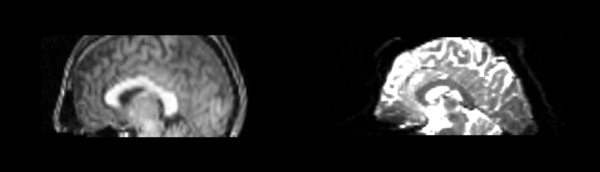

Affine

- 53-t2 -> 31-t1 = aff1

- aff1 -> 53-t2 = aff2

The image shows these side by side. The are nearly the same except for the loss of fine detail.